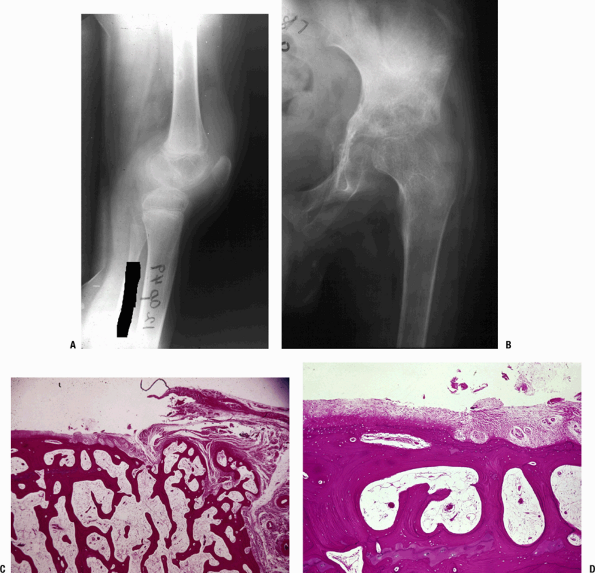

joint space (Fig. 27.2-2)P.512![]() Figure 27.2-2 (A) Figure 27.2-2 (A)

TB of the knee. When TB first lodges in the synovium of a joint, it

creates many tubercles (usually small, without caseation) and induces

marked synovial proliferation. The suprapatellar pouch in this knee is

filled with inflamed synovium with histology as in Figure 27.2-1. There is significant osteopenia. (B–D) TB of the hip. (B)

Once the infection is established, the inflamed synovium invades the

joint space from the margins, growing as a pannus as in rheumatoid

arthritis, destroying the underlying cartilage by interfering with the

diffusion of nutrients to the cartilage. The joint surface is usually

preserved centrally until the process becomes much more advanced.

Synovial pathology involves both sides of the joint. TB must be in the

differential diagnosis for any periarticular disorder involving more

than one bone around a joint area or marginal erosions. (C) Photomicrograph of the edge of a joint showing the pannus growing from the right onto the underlying articular cartilage. (D) This higher-power view shows complete destruction of the cartilage by the pannus.